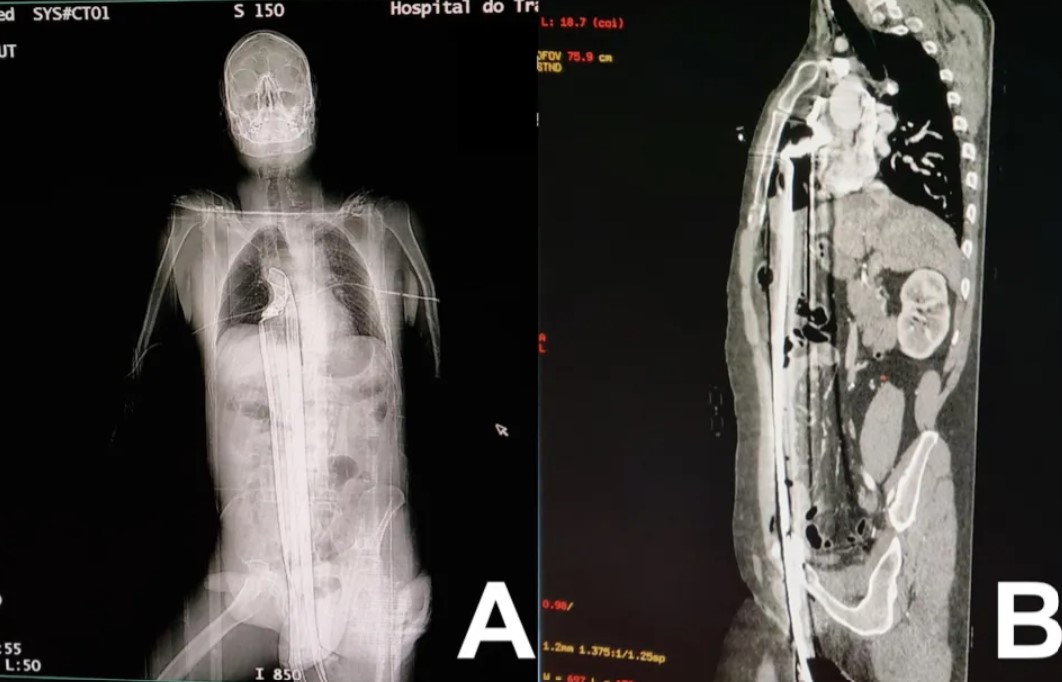

大難不死必有好福!《國際外科雜誌病例報告期刊》於日前分享一則病例,指一名57歲巴西男子從高處墜落後,被一根長約91cm的鋼條從下體插入幾乎貫穿全身,但經過醫生緊急治療後,男子奇蹟般康復。不僅如此,他還住了加護病房僅3日,就轉為普通病房休養,康復速度十分良好。

綜合外媒報報導,《國際外科雜誌病例報告期刊》於日前指出,一名57歲巴西男子被送到「Complexo Hospitalar do Trabalhador」醫院,經過檢查後,發現他的傷勢嚴重,他的會陰(生殖器和肛門之間的脆弱皮膚)被一條91cm的鋼條插入,並延伸穿過他的腹部與胸部,還險些觸及他的心臟,有如「人肉串」。雖然該男子的肝臟已經被刺穿,但心律、血壓與血氧都穩定。

由於當時情況緊急,男子緊急被安排手術,當時醫生在他身上開了從下腹到胸骨的開口,才順利的把鋼條取出來。該男子在術後僅僅住了3日的深切治療部病房,就轉到了普通病房,而且還沒有任何後遺症,可見恢復良好。